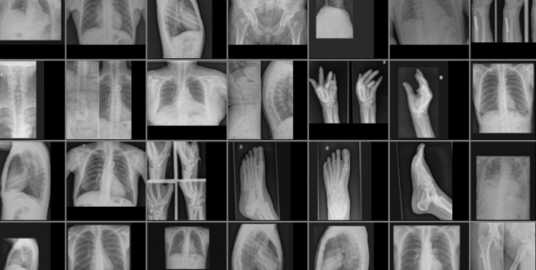

身体部位X射线图像数据集

数据集下载地址:http://m6z.cn/5yth1K

本数据集收集了来自身体各部位的X光图片